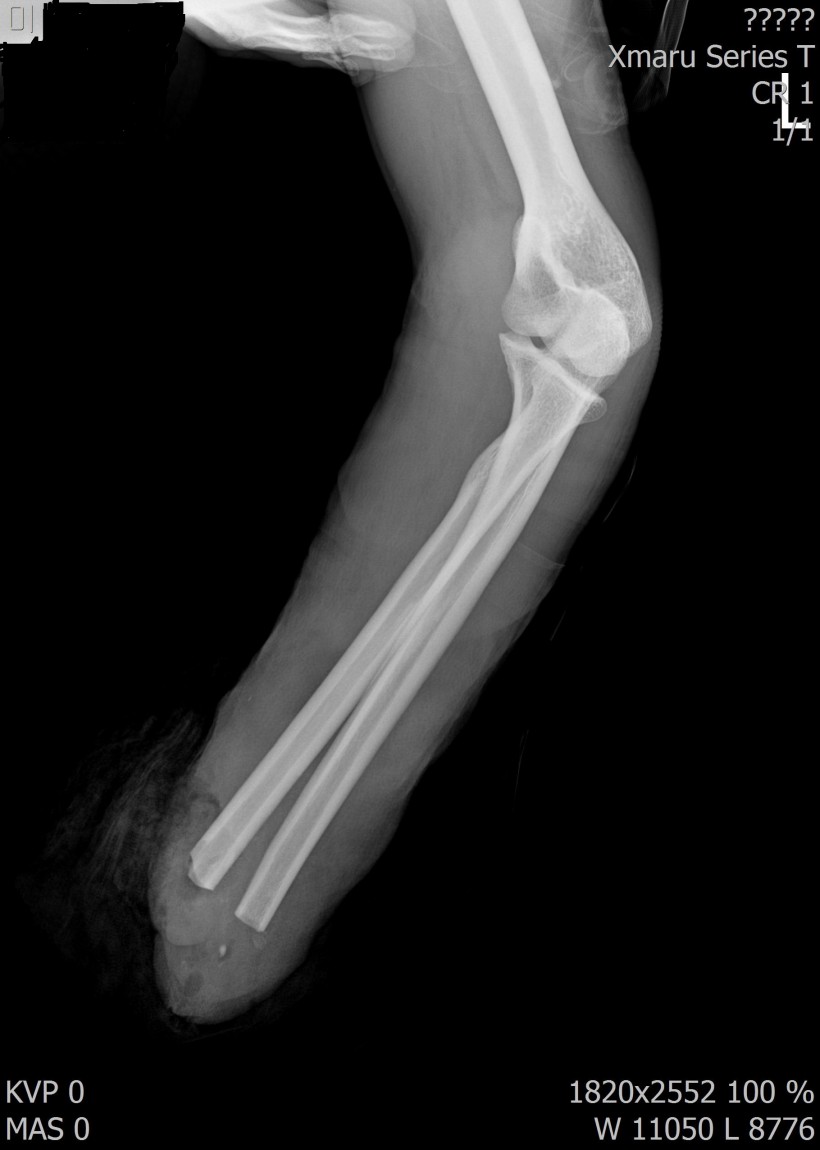

2017년 12월 23일 좌측 손목 절단 ( 치료 과정 모습)

20171223일 당시 ( 외국인 미 **)께서 좌측 손목 전달되어 본원 방문함.

2018.115일 현재 치료 중인 환자에 대하여 .....